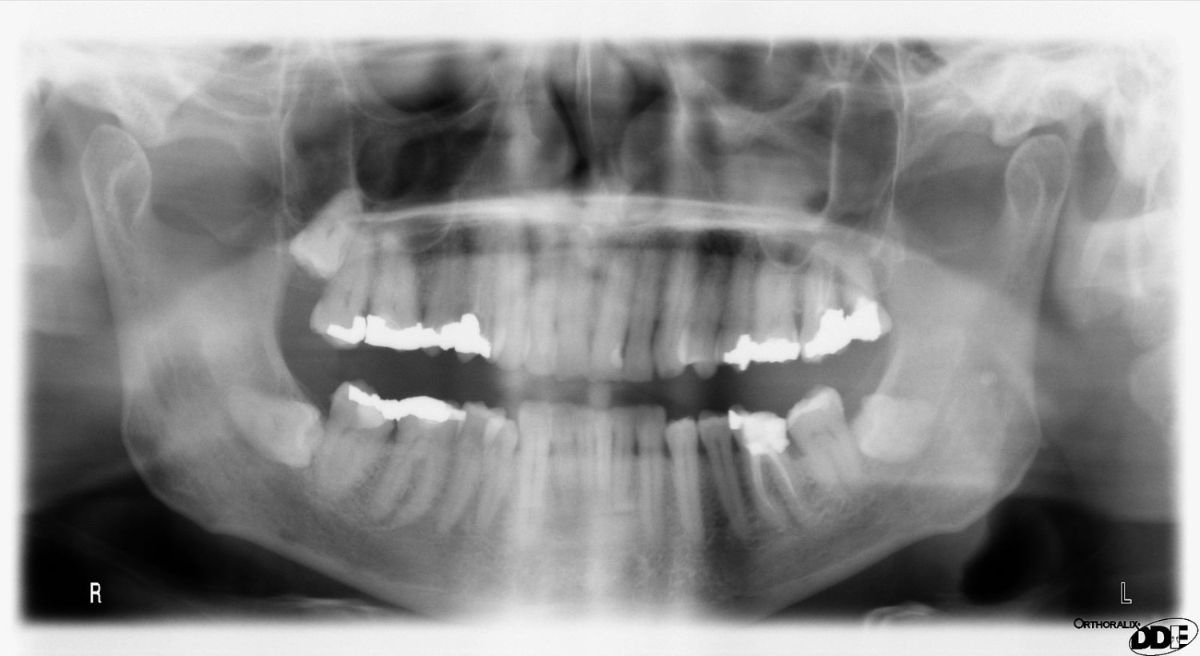

If you have issues with facial asymmetry, there’s a good chance you already know about it and have wondered what could be done. Well, luckily, Dr. Laidlaw and her skilled team have plenty of experience in correcting facial asymmetry with curing edge options. We are able to evaluate the relationship between your facial features and your oral health to create a treatment plan that best fits your needs! Let’s look at a few ways we can help.